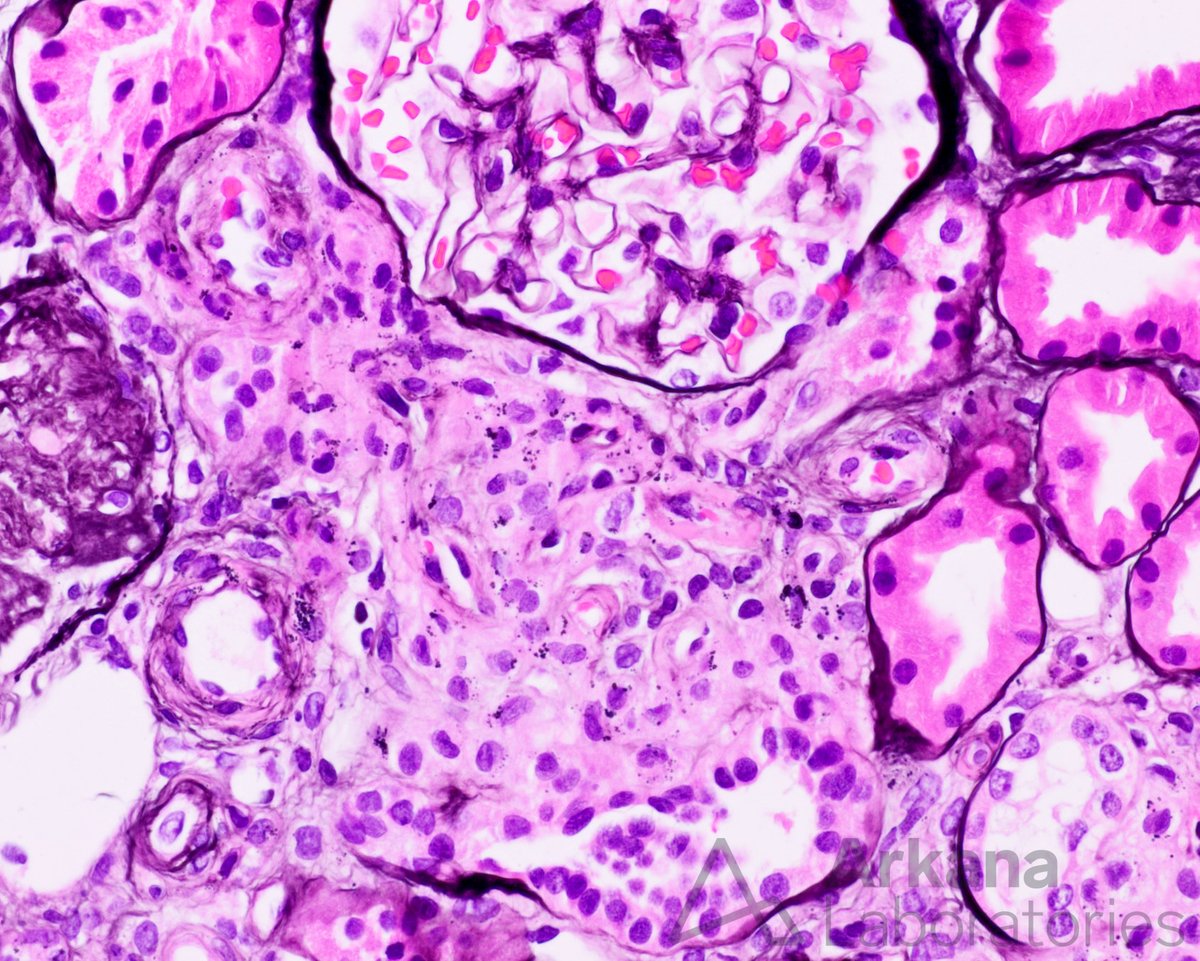

@arkanalabs

Arkana Laboratories

3 years

What is your diagnosis for this finding in a young patient with renal artery stenosis? #DiagnoseThis